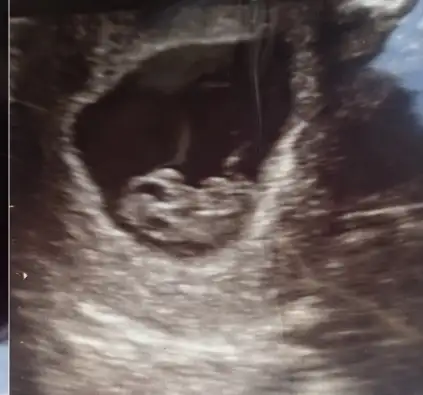

Gözünüz aydın sağlıkla alın kucağınızaMerhaba arkadaslar, ben de Rabbım nasip ederse ocak annesi olacağım, bugun 6+5iz, tüp bebek ile gebe kaldım, insallah bol bol bılgı alısverısı yaparız burada![]()

Merhaab son adet döneminiz ne zaman sanırım aynıyız tarihlerde :)Bebişim gördüm kalbini duydum çok şükürnormalde 6+4 üm ama şuan 6+1 görünüyormuş ama her şey normal dedi